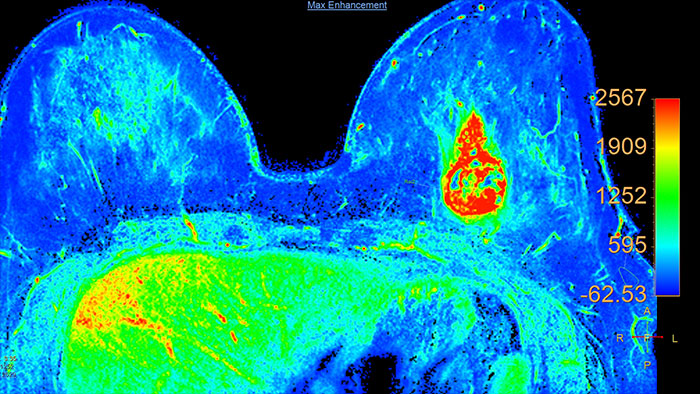

Improve image contrasts for MR data in dynamic studies

MR Subtraction enables subtraction calculations of dynamic studies and also provides for computation of magnetization transfer contrast ratio (MTC) images from an appropriate set of input images.

Benefits